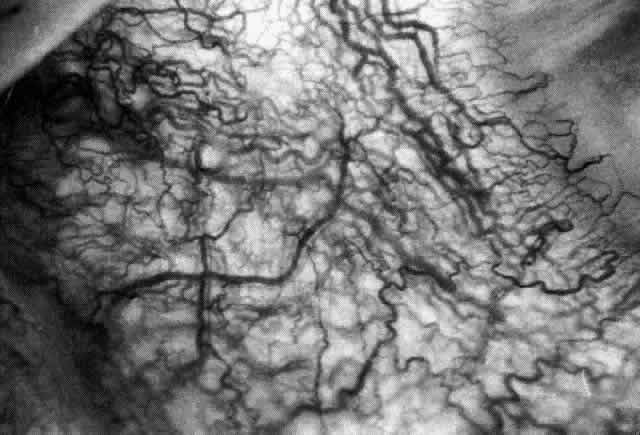

Simple and nodular episcleritis differ in their clinical courses, but in both the edema and infiltration are entirely within the episcleral tissues. The sclera is not involved. The maximum congestion is in the superficial episcleral network, with some slight congestion of the conjunctival vessels and deep episcleral vessels (Fig. 10). The intraocular structures are not involved in either variety, nor is the visual acuity affected. Anterior segment fluorescein angiography reveals a normal vascular pattern but a very rapid flow rate, with the whole transit of the dye being completed within 2 or 3 seconds (Figs. 11 and 12).

Fig. 10. Maximum congestion in the superficial vascular plexus in episcleritis. The conjunctival and deep episcleral networks are separated from the deep plexus by edema and infiltration in the episcleral tissue. (Watson PG, Hayreh S, Awdry P: Episcleritis and scleritis. Br J Ophthalmol 52(3):278–279, 1968)

The redness of simple episcleritis may be intense, varying from a fiery-red or a brick-red discoloration to a mild red flush, but it does not have the bluish tinge that is seen in scleritis. The distribution is usually sectorial but can involve the whole anterior segment of the globe. The episcleral vessels are engorged but retain their normal radial position and architecture (Figs. 13 and 14; Color Plate 1A). In simple episcleritis, there is a diffuse edema of the episcleral tissues. These tissues are sometimes infiltrated with gray deposits that appear yellow in red-free light. Surprisingly, the eye is rarely tender to the touch.

Fig. 13. Infiltration of the episclera in which the superficial episcleral vessels show maximal congestion. Conjunctival vessels are slightly congested, as is the deep episcleral plexus, whose irregular criss-cross pattern can be seen deep to the radially arranged superficial episcleral plexus.

Fig. 14. Diffuse inflammation. Superficial vessels are maximally engorged and retain their radial pattern and architecture. (See Figures 27 and 34.) (Watson PG: Connective tissue disorders and the eye. In: Recent Advances in Ophthalmology, Vol 5, pp 214–277. London, Churchill-Livingstone, 1975)